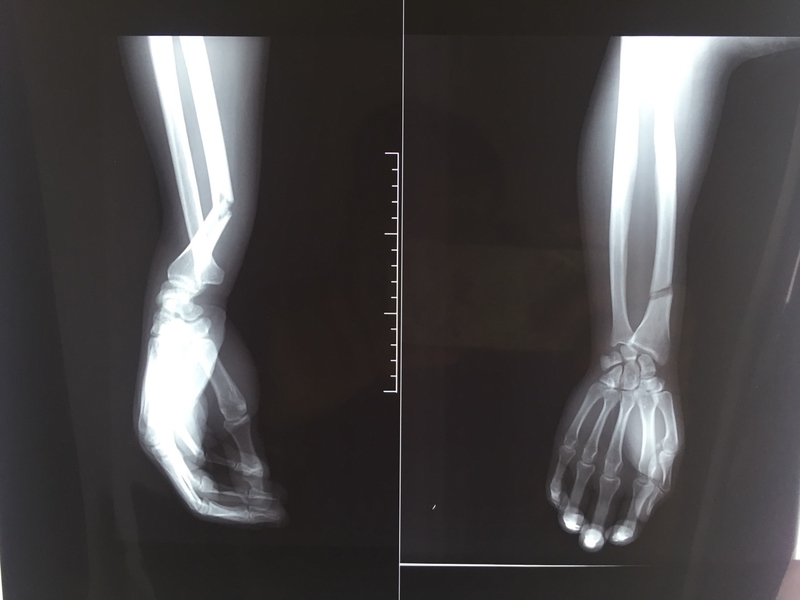

Các bước sơ cứu và băng bó cho người gãy xương cẳng tay 1 Hình ảnh X-quang chụp xương cẳng tay bị gãy